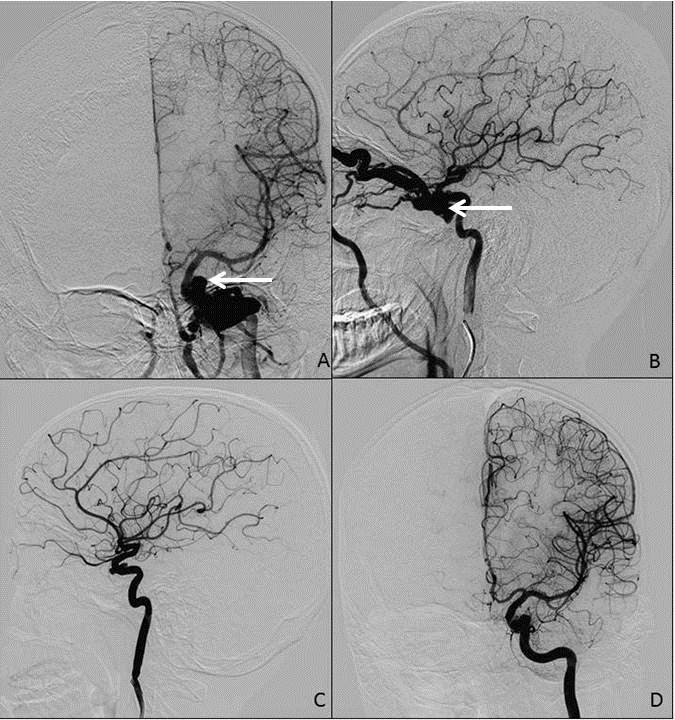

Selective digital subtraction angiography of left internal carotid artery (ICA) confirmed a direct fistulous opening of medial wall of ICA into the cavernous sinus. The fistula was draining through the left superior ophthalmic vein into the angular and jugular veins. Dilatation and increased tortuosity of the left superior ophthalmic was also noted with no retrograde venous drainage into the cerebral and petrosal venous systems (figure 3). The right ICA and vertebro-basilar circulation showed normal vasculature.

While awaiting definitive treatment, the patient was advised to sit on armless chair and compress his left carotid artery with his hand about 15-20 times a day with duration of compression as per tolerance. After two weeks, the patient was prepared for a definitive endovascular procedure; however during the procedure the pre-embolization injection of left ICA showed that carotid-cavernous fistula had spontaneously thrombosed with subtle contrast spillage at the site of previous fistula (figure 3). The procedure was abandoned after completing the protocol of diagnostic angiography, which was also found to be normal.

Figure 3: DSA of left ICA showing fistulous communication at left CS with abnormally enlarged veins, prominent in arterial phase (A, frontal) and dilated, tortuous superior ophthalmic vein draining into prominent facial vein (B, lateral). DSA of left ICA after 2 weeks showing that carotid-cavernous fistula no more visible and no prominent veins in arterial phase (C) frontal projection, (D) lateral view. Figures C and D suggest that the CCF is repaired by thrombosis.